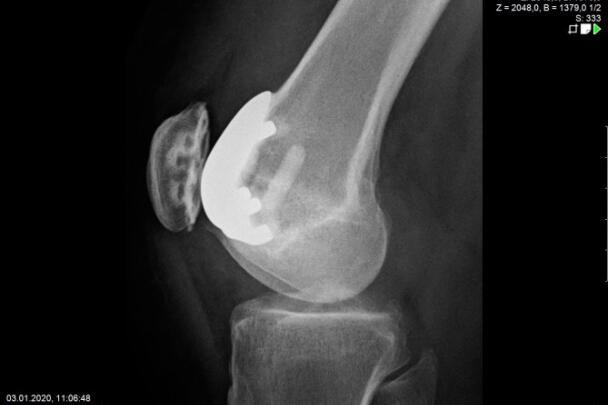

Endoprosthetics of the knee joint is an effective procedure for the treatment of symptomatic advanced wear and tear of the knee joint (gonarthrosis). If the X-ray shows a complete loss of joint space width under load, the complaints persist for more than 6 months, and the conservative therapy options have been exhausted, there is probably an indication for treatment with an artificial joint replacement (endoprosthesis). It must then be clarified which type of prosthesis is required, because today we have a large number of implants available. We distinguish between partial joints and full prostheses, and in the case of full prostheses we again distinguish between the degree of coupling of the prosthesis. If only parts of the joint are affected, only these have to be replaced and partial joints can be used. The so-called sled prostheses on the inner and outer side of the knee joint, as well as the sliding bearing replacement for problems on the kneecap, have both proven themselves effective. With full prostheses, we again differentiate between the degree of coupling of the prosthesis. Anterior and posterior cruciate ligament-supporting prostheses (surface replacement) partially coupled implants that support the inner and outer ligaments and coupled implants for complete loss of knee ligament and capsular function are used. Partially and fully coupled prostheses usually have to be inserted with stem components.

The knee prostheses are usually cemented in place, but cement-free implants are also available, which can be used, for example, in cases of cement allergies or very young patients.